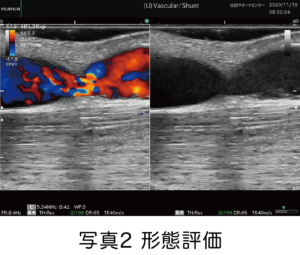

そのような場合、超音波診断装置を使用してシャントに流れている血流量(シャント血流量Flow Volume:FV)や血液の流れにくさ(血管抵抗指数Resistance Index:RI)など、血液透析を行うに十分な能力を持っているかを評価する「機能評価(写真1)」と血管全体の把握や機能低下の原因となっている病変部の詮索(狭窄の程度)などを評価する「形態評価(写真2)」を行っております。